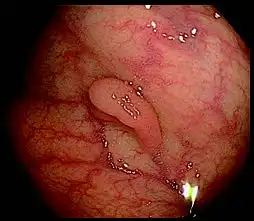

该电子结肠镜将图像放大80x*,其高清图像质量清晰地获得粘膜表面的近距离视图。结合更亮的NBI(窄带成像),粘膜组织和毛细血管网络得到增强,进一步支持详细观察。

白光 使用NBI进行光学80x放大